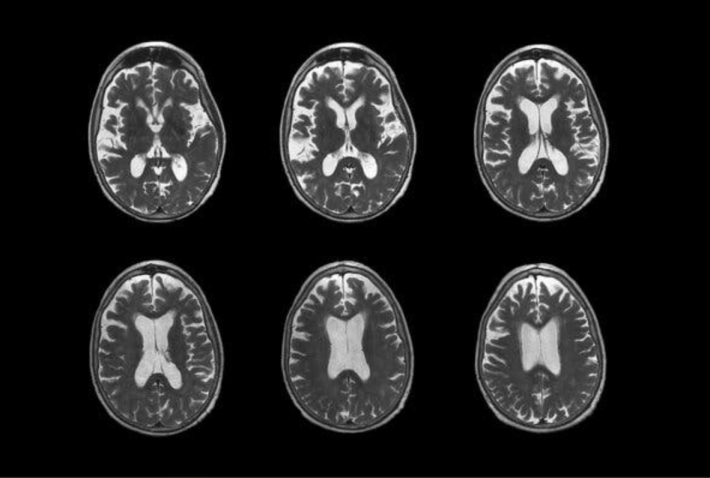

Foto d'archivio

La Food and Drug Administration americana autorizza l’atteso farmaco per l’Alzheimer di Eisai e Biogen. Negli studi eseguiti il Leqembi ha mostrato risultati promettenti per la cura della malattia, da cui sono affetti circa 6,5 milioni di americani, con un evidente rallentamento della malattia.